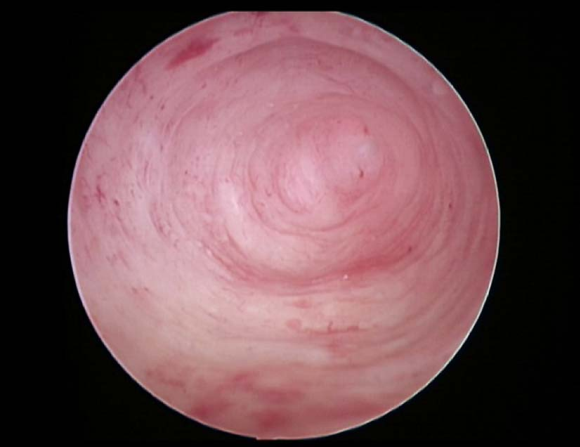

单角子宫宫腔镜下表现

不完全纵隔子宫宫腔镜下表现